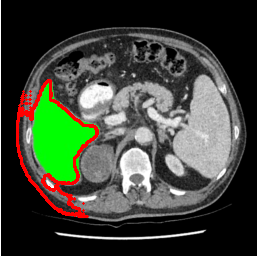

| U-Net | nnU-Net | TransU-Net | SAM-PP-0 | SAM-PP-5 |

| SAM-PP-50 | SAM-PP-100 | SAM-Mix-5 | SAM-Mix-50 | SAM-Mix-100 |

Our primary findings comparing the proposed model to baseline fully-supervised models when segmenting the liver from the LiTS dataset are reported in Table 1. The reported results demonstrate that our SAM-Mix model consistently achieves higher Dice scores compared to the fully supervised baselines as well as the two-stage SAM-PP method. Against U-Net, the best-performing fully supervised method, the SAM-Mix variant trained on 50 segmentation labeled slices (SAM-Mix-50), achieves a Dice score improvement of 5.9%. In terms of Hausdorff distance, while the fully-supervised baselines do slightly outperform SAM-Mix-5 and SAM-Mix-100, SAM-Mix-50 does achieve a lower Hausdorff distance by 22.38%. Qualitative evaluation as shown in Figs. 3 further affirms the superiority of SAM-Mix over baseline and existing fully-supervised methods as well as the two-stage SAM-PP variants. Furthermore, the boxplot visualization in Fig. 2 showcases consistently improved performance by SAM-Mix outperforming all the fully supervised and semi-supervised methods.